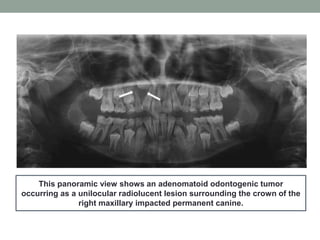

This panoramic view shows an adenomatoid odontogenic tumor

occurring as a unilocular radiolucent lesion surrounding the crown of the

right maxillary impacted permanent canine.

This panoramic viewshows an adenomatoid odontogenic tumor occurring as a unilocular radiolucent lesion surrounding the crown of the right maxillary impacted permanent canine.